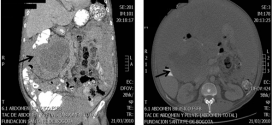

Leer MásNEOPLASIA MALIGNA DE LA VÍA BILIAR

La neoplasia maligna de la vía biliar. Es una enfermedad por la cual se forman células malignas cancerosas en los tejidos de la vesícula biliar es una enfermedad poco frecuente por la que se encuentran células cancerosas en los tejidos de la vesícula biliar. Tumor maligno en general y especialmente el formado por células epiteliales, a saber. Los canceres se …